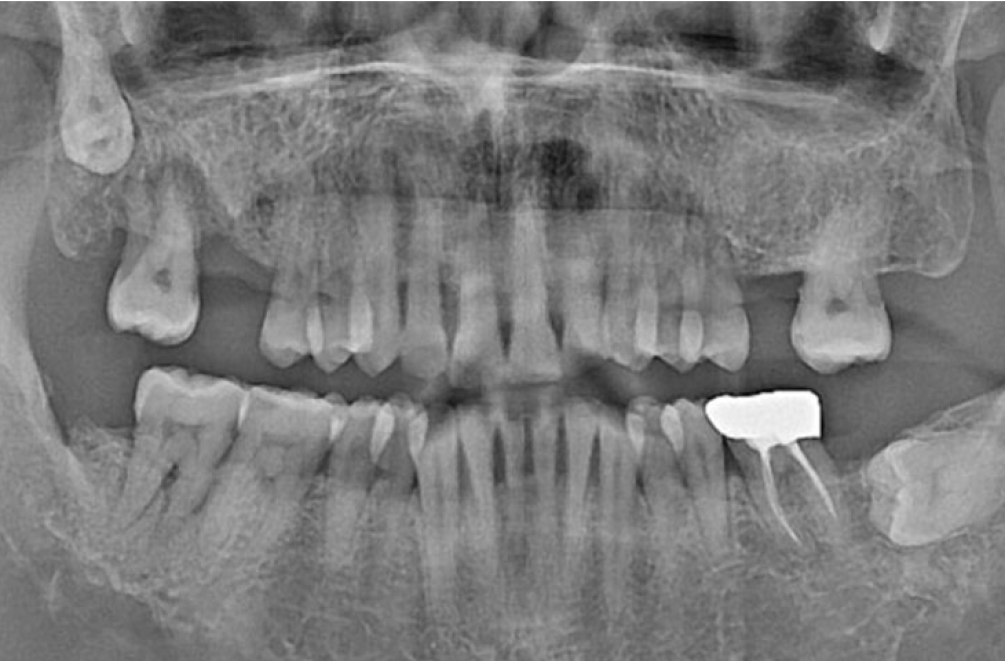

• BEFORE

오른쪽 하악 매복 사랑니 발치 Before X-Ray

치료시작일

2020.04.24

AFTER

오른쪽 하악 매복 사랑니 발치 After X-Ray

치료종료일

2020.06.24

오른쪽 하악 매복 사랑니 발치